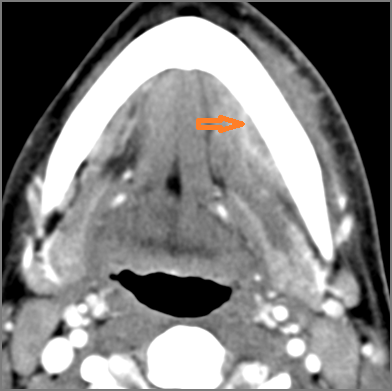

There is excessive enhancement or thickening of the fat or other soft tissues within or surrounding the buccal space, masticator space, floor of the mouth, submandibular space or the adjacent superficial fascia or subcutaneous fat and skin. [Yes/No]

There is edema or abscess within the fat of the adjacent parapharyngeal and retropharyngeal space. [Yes/No]

There is edema or abscess within the adjacent parapharyngeal and retropharyngeal spaces. [Yes/No]